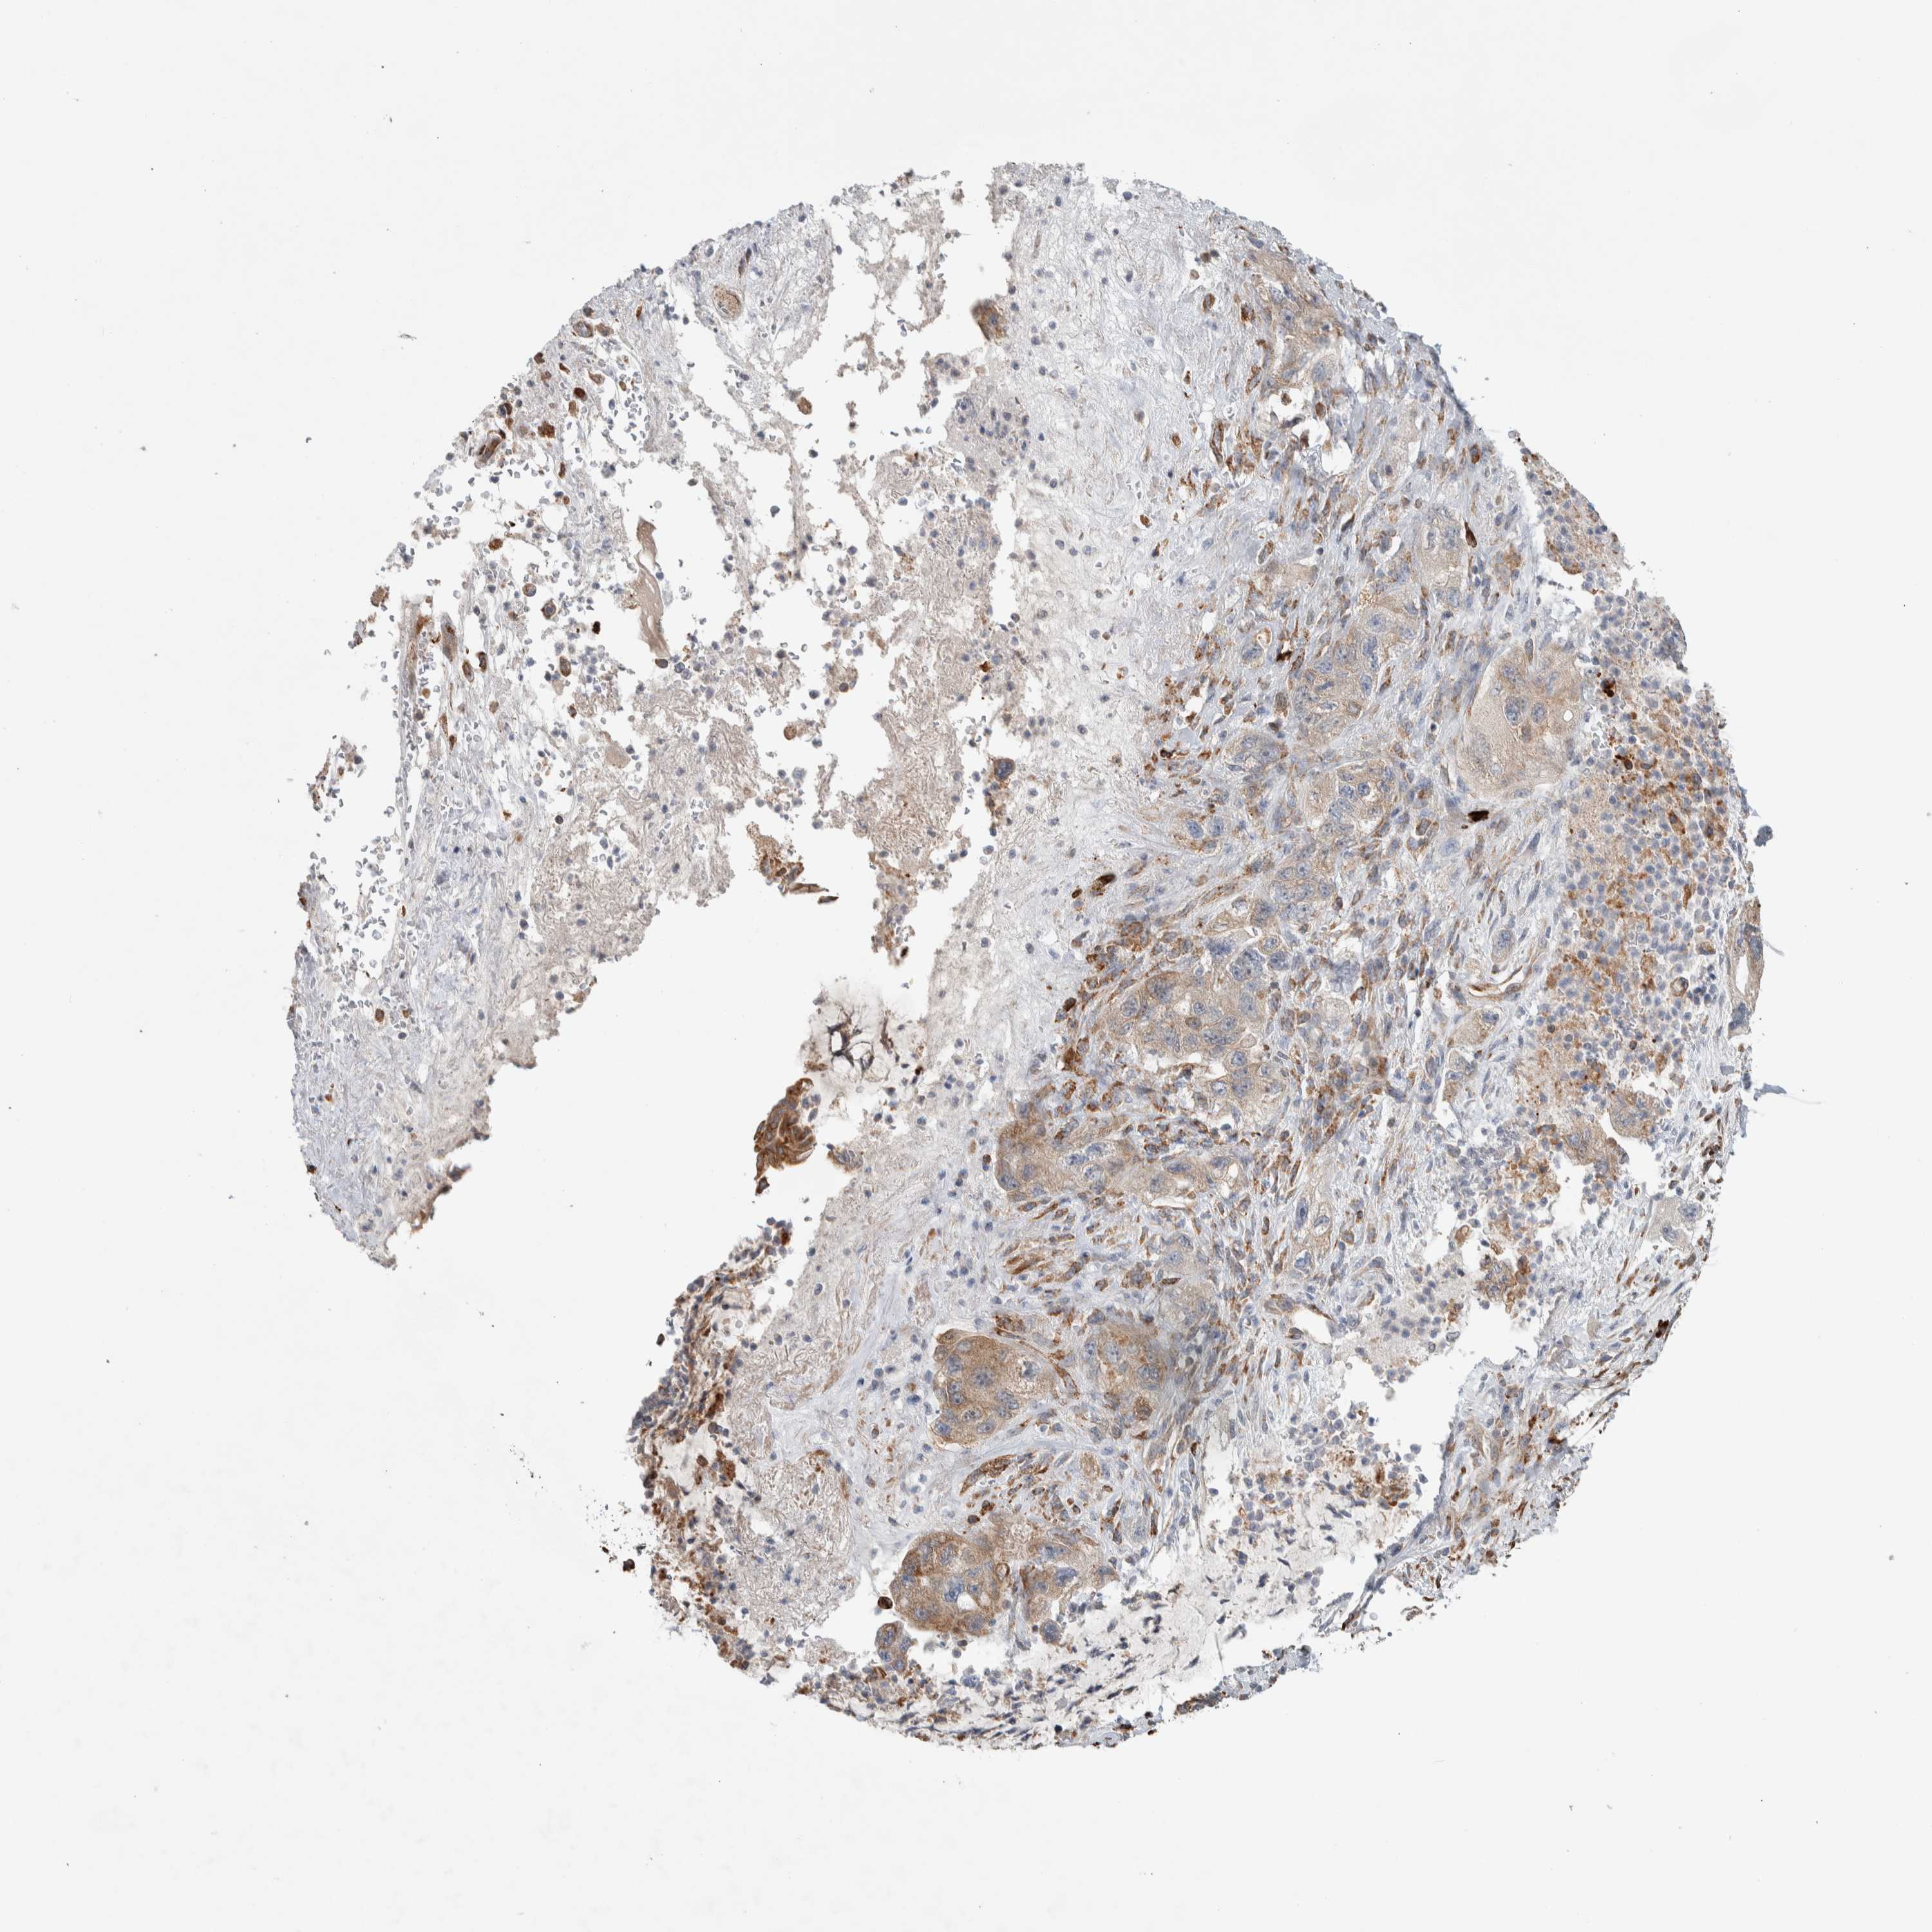

PANCREATIC CANCER - Protein expressioni

A mouse-over function shows sample information and annotation data. Click on an image to view it in a full screen mode. Samples can be filtered based on level of antibody staining by selecting one or several of the following categories: high, medium, low and not detected. The assay and annotation is described here.

Note that samples used for immunohistochemistry by the Human Protein Atlas do not correspond to samples in the TCGA dataset.

Antibody stainingi

Antibody staining in the annotated cell types in the current human tissue is reported as not detected, low, medium, or high, based on conventional immunohistochemistry profiling in selected tissues. This score is based on the combination of the staining intensity and fraction of stained cells.

Each image is clickable and will lead to virtual microscopy that enables deeper exploration of all samples and also displays staining intensity scores, fraction scores and subcellular localization as well as patient and tissue information for each sample.

Antibody HPA024291

Antibody CAB018652

Staining

High

Medium

Low

Not detected

Intensity

Strong

Moderate

Weak

Negative

Quantity

>75%

75%-25%

<25%

None

Location

Nuclear

Cytoplasmic/membranous

Cytoplasmic/membranous,nuclear

Adenocarcinoma, NOS